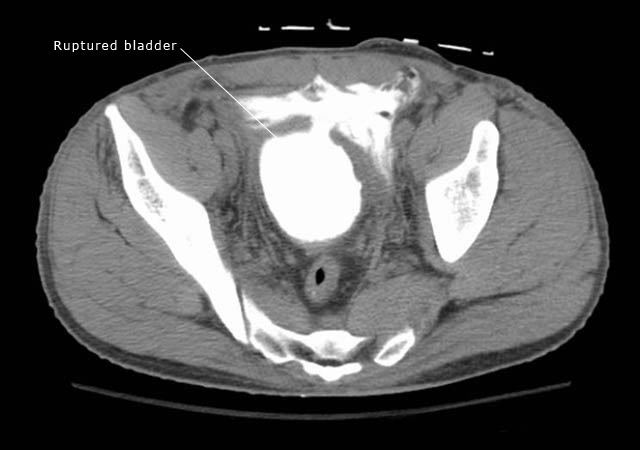

CT cystogram